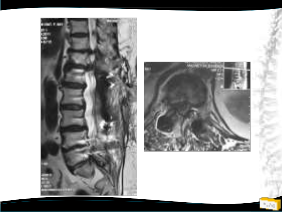

Olgu

• 64y, K

• Bel ve her iki bacak ağrısı

• NM normal

Yapılan Ameliyat: L1-L5 dekompesyon + transpediküler stabilizasyon

• Bel ağrısı, bacaklarında güçsüzlük,

3/5 paraparezi, üriner retansiyon

1. Op: Torakotomiyle T12-L1 diskektomi